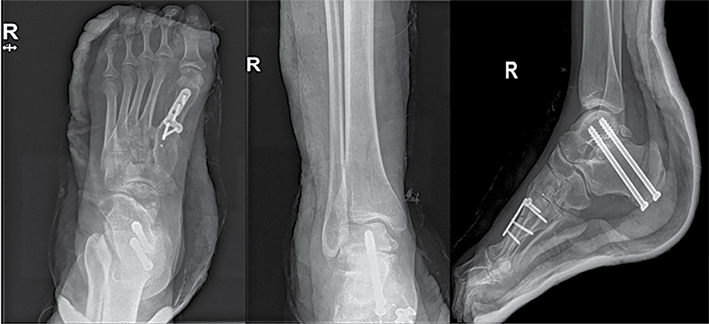

Po metų pacientė atvyko dėl dešinės pėdos nestabilumo, sunkumo vaikščioti. Sudėtinga pritaikyti avalynę, konservatyvus gydymas neefektyvus. Rentgeno nuotraukose matyti dešinės pėdos varus tipo deformacija, aukštas pėdos skliautas. Čiurnos ir pėdos funkcija pagal AOFAS – 67 balai, pagal EFAS – 18 balų. Pacientei atlikta uždaro kampo kulnakaulio ašį koreguojanti osteotomija, lateralizuotas gumburas, atlikta subtalarinio sąnario artrodezė dviem sraigtais. Hoke metodika pailginta Achilo sausgyslė. Atlikta I padikaulio uždaro kampo kylinė osteotomija ir osteosintezė L formos 5 skylių plokštele ir 4 rakinamais sraigtais. Po operacijos koja imobilizuota gipso langete, skirti analgetikai ir vaistai nuo trombų susidarymo. Pritaikytas ortopedinis įtvaras. Rekomendacijos išliko tokios pat, kaip ir po kairės kojos operacijos. Kontrolinės apžiūros duomenų dar negalima vertinti, nes operacija atlikta neseniai.

7 pav. Dešinės čiurnos ir pėdos rentgenogramos po operacijos